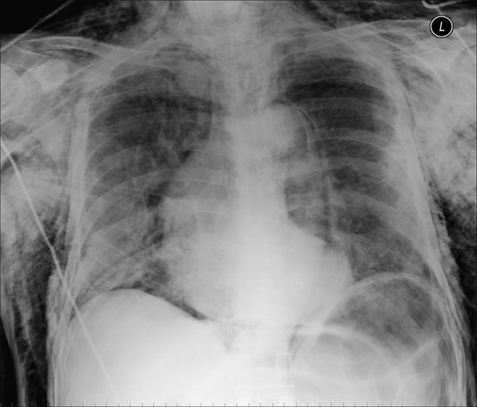

Figure 32.15 Male. Age 23. RTA. Left-sided rib fractures (note that a flail segment is present). Pneumothorax. The consolidation in the left upper lobe is an area of lung contusion.